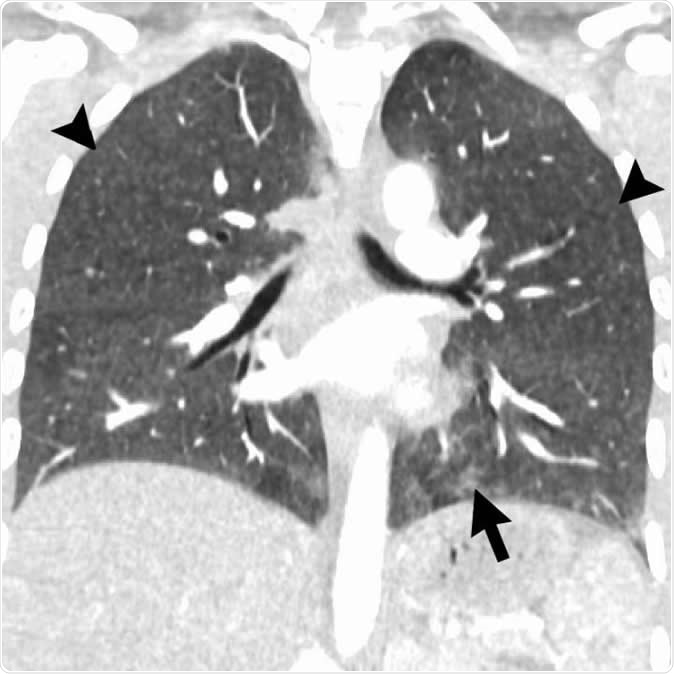

Coronal image shows hypersensitivity pneumonitis (HP) pattern in a 35-year-old man who vaped tetrahydrocannabinol products. Extensive hazy centrilobular nodularity (arrowheads) is most pronounced in midlung and upper lung zones consistent with inhalational injury. Mild ground-glass opacity is present as bases (arrow). This imaging pattern is commonly seen in HP. Patient

Coronal image shows hypersensitivity pneumonitis (HP) pattern in a 35-year-old man who vaped tetrahydrocannabinol products. Extensive hazy centrilobular nodularity (arrowheads) is most pronounced in midlung and upper lung zones consistent with inhalational injury. Mild ground-glass opacity is present as bases (arrow). This imaging pattern is commonly seen in HP. Patient's condition rapidly improved after steroid administration and no biopsy was obtained. Although authors have seen a few cases with HP pattern, there are no cases in literature with pathologic confirmation. Other possible etiologies for diffuse pattern of centrilobular nodules in electronic cigarette or vaping product use-associated lung injury includes airway-centered foci of organizing pneumonia. Image Credit:  Radiological Society of North America